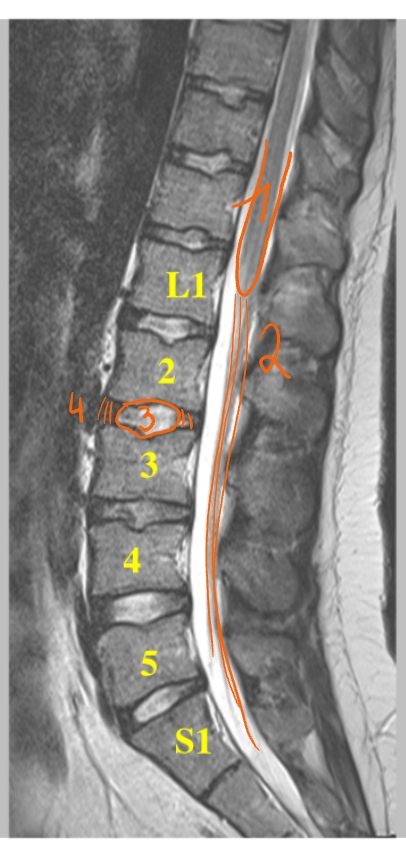

MRI

= magnetische resonantie

werkt met magneetvelden & radiogolven → dus niet met röntgenstralen

2 soorten MRI-beelden

T1-beeld

water & CSV (cerebrospinaal vocht) = donkergrijs

T2-beeld

water (en CSV) = wit

(WWW)

→ beeld in het mediosagittaal vlak

arcus anterior

arcus posterior

discus intervertebralis (= tussenwervelschijf)

embryonaal restje van de discus tussen C1 & C2

medulla spinalis

→ 1e foto = T1-beeld

→ 2e foto = T2-beeld

cervicale lordose

thoracale kyphose

lumbale lordose

conus medullaris

cauda equina (= paardenstaart)

nucleus pulposus

annulus fibrosus

→ MRI: T2-beeld

discus is donker in het midden = uitgedroogd

begint te verslijten → 1e stadium van degeneratief discuslijden